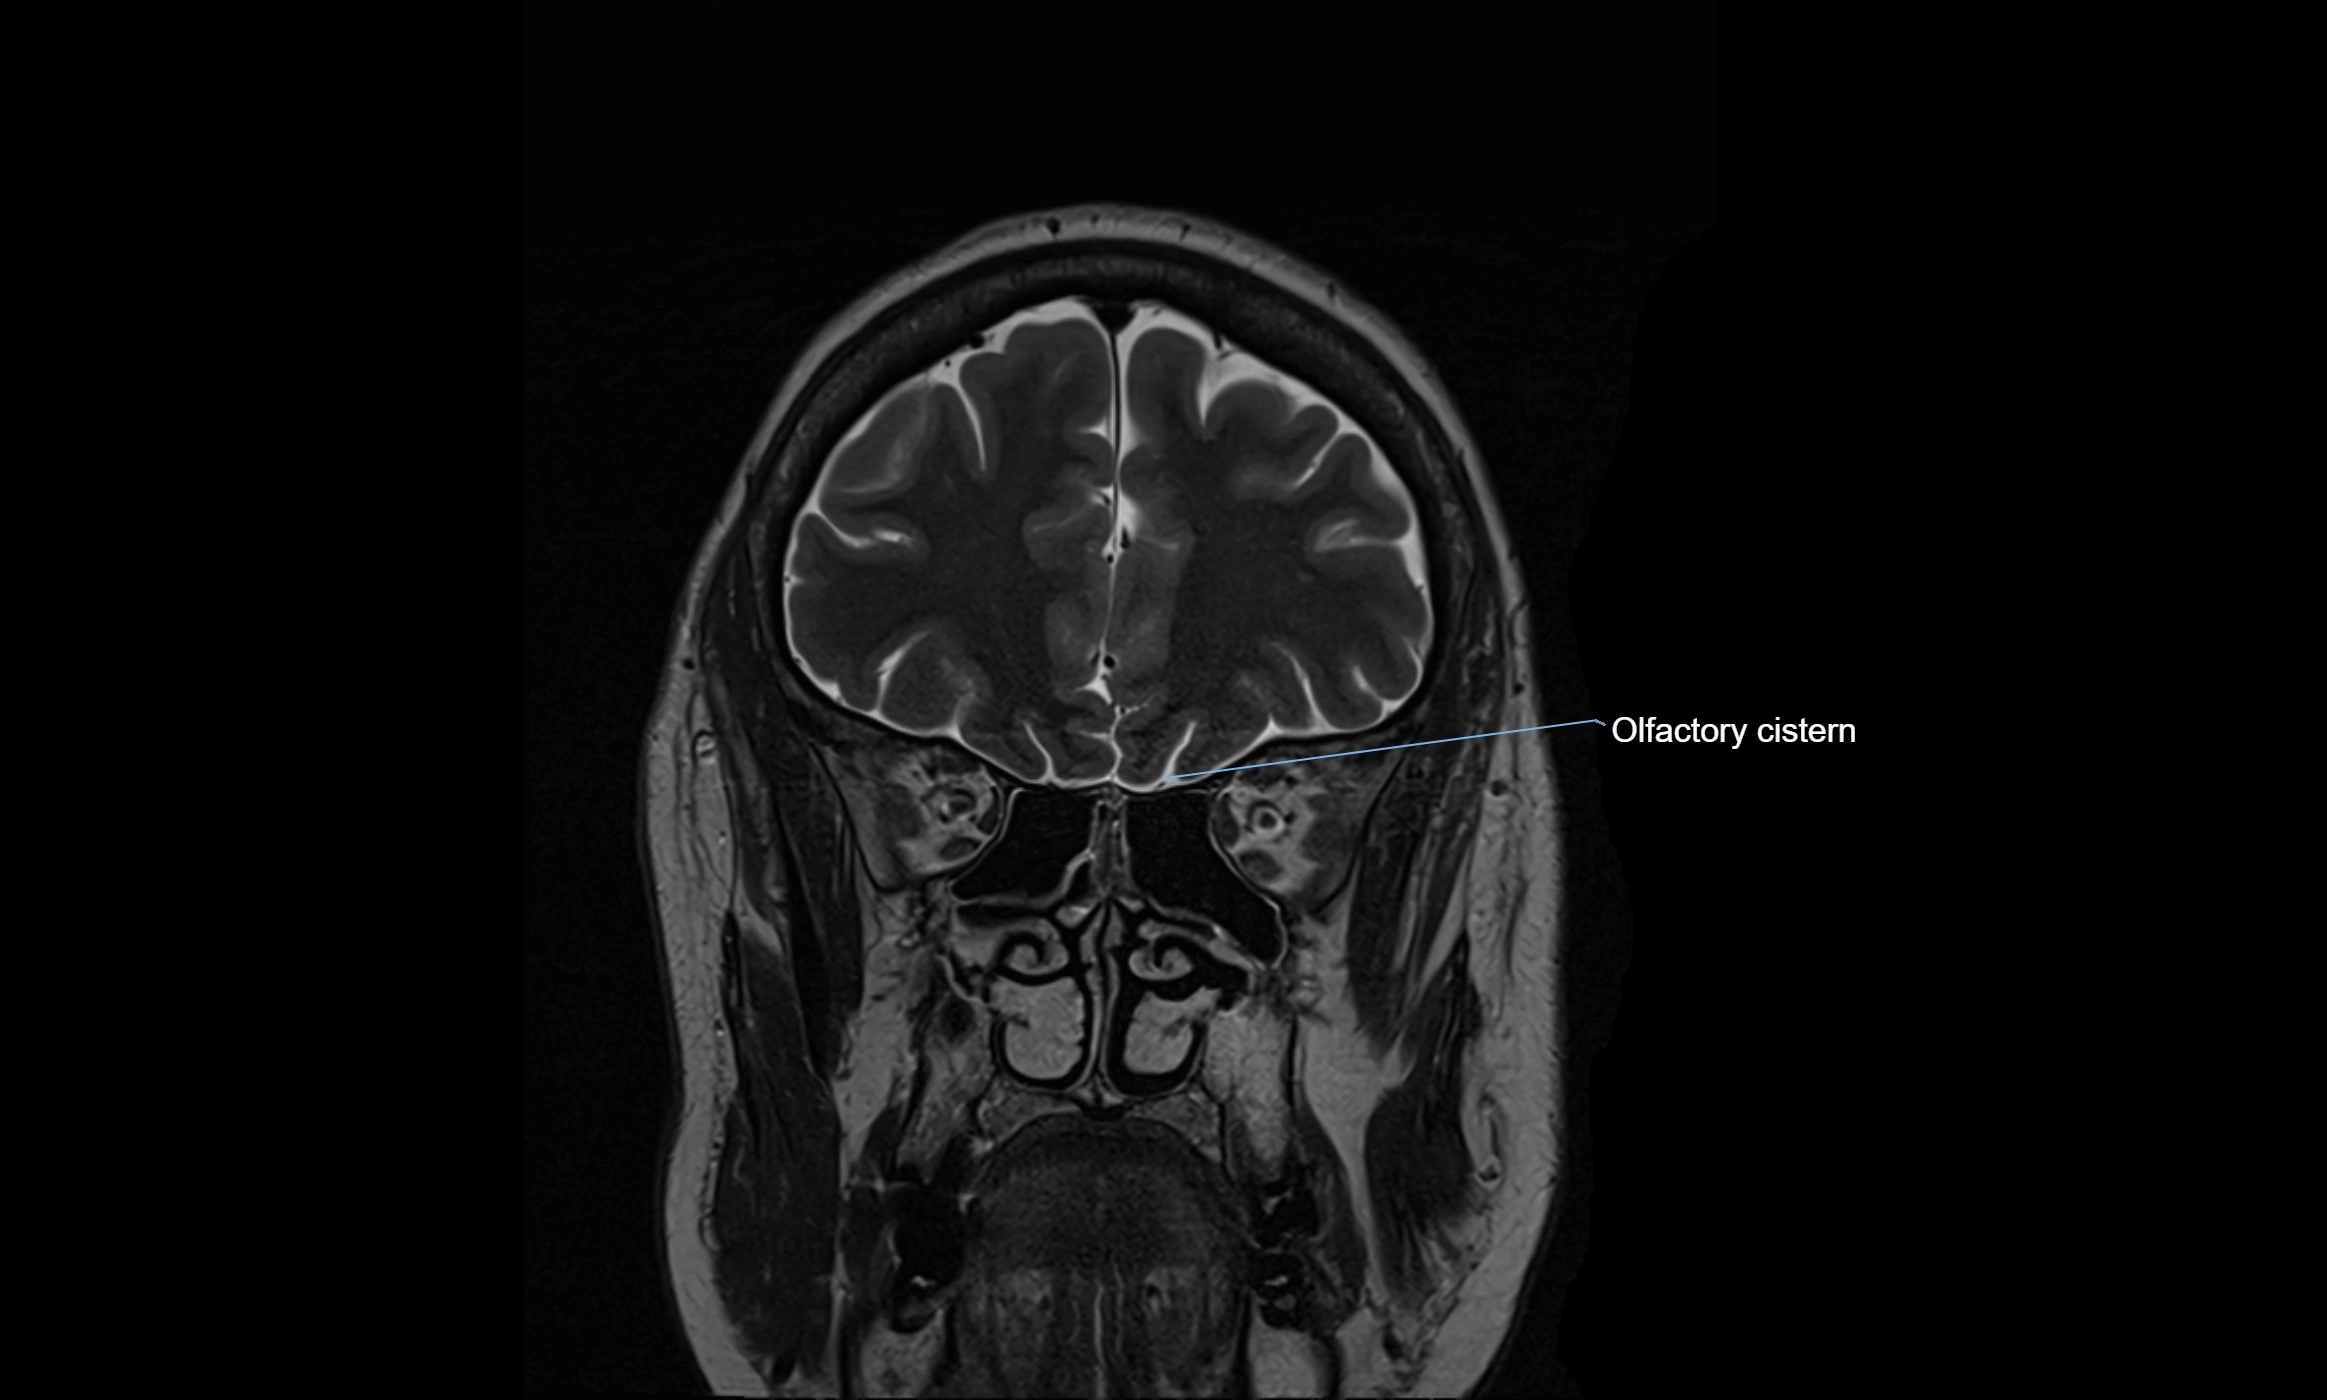

CT image

image